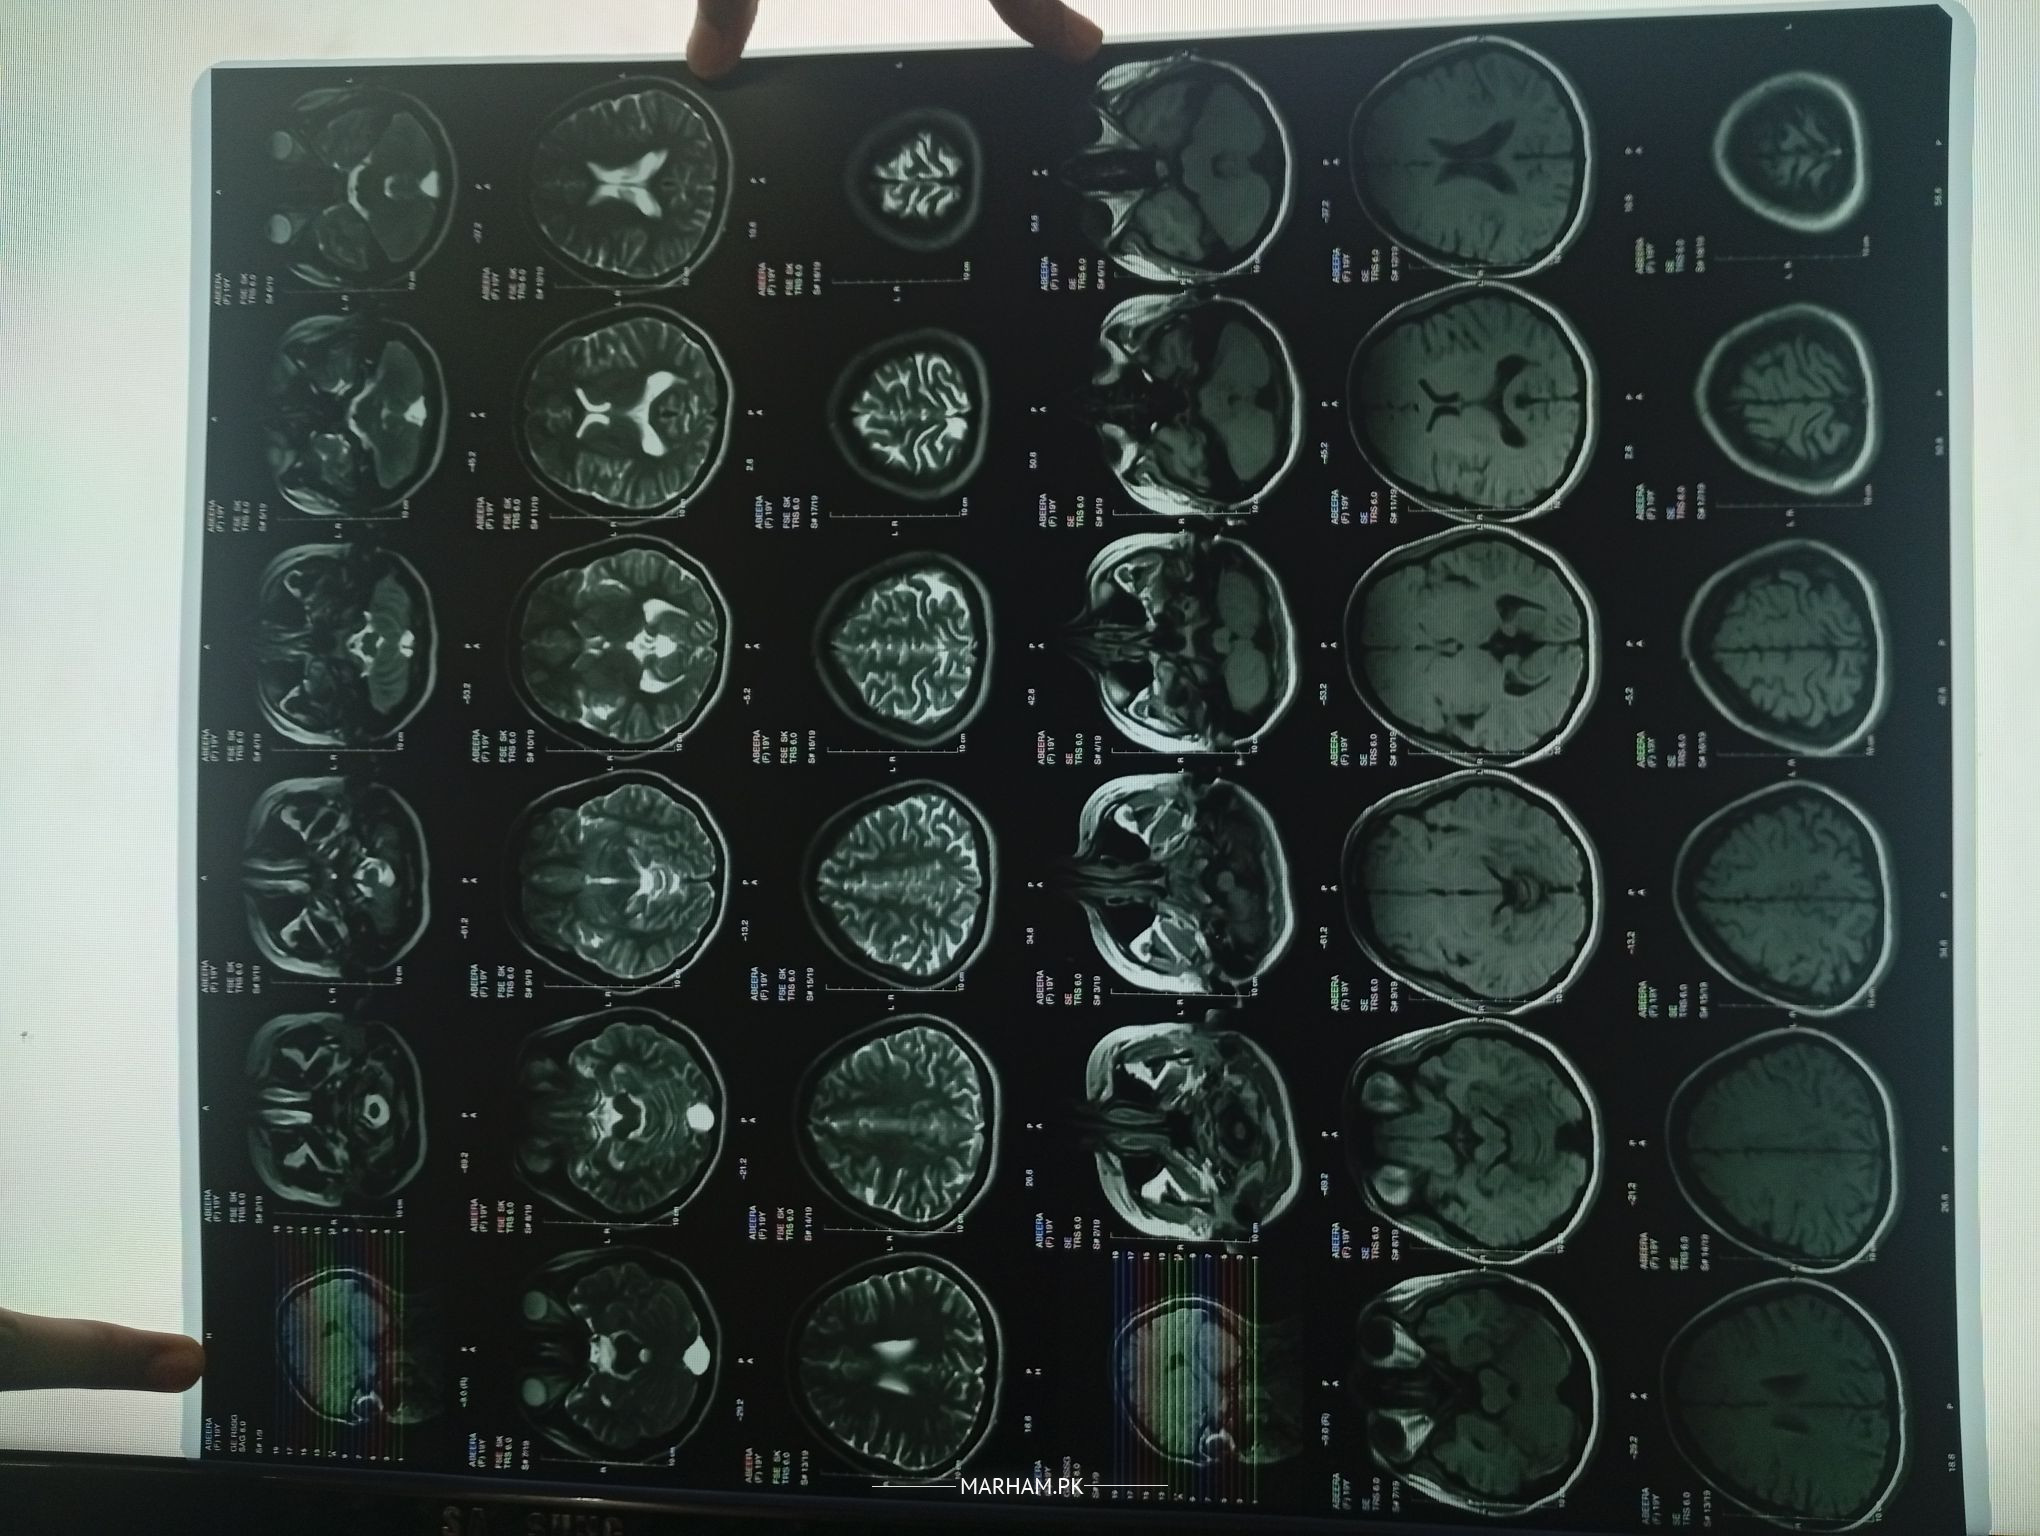

The MRI at first glance appears normal, though the report is awaited.

Need more information about the headache before can guide further.